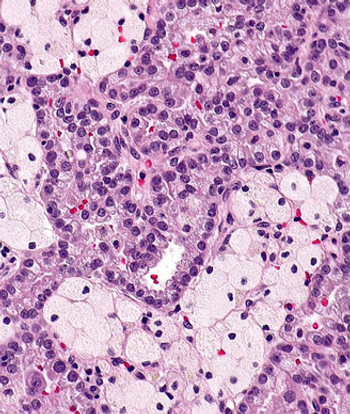

Patients who experienced early relapse of multiple myeloma after undergoing autologous stem cell transplantation had worse progression-free and overall survival.